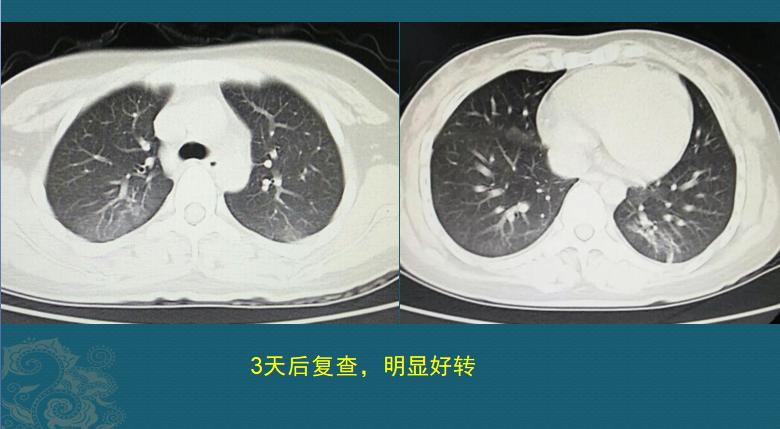

抢救溺水患者,时间就是生命!多亏救生员急救措施合理,时间没有耽搁,住院后经过吸氧、祛痰、消炎、保肝等治疗后很快好转,没有留下后遗症!上图是她住院第3天复查的CT,肺部磨玻璃影以一种很快的速度吸收了。